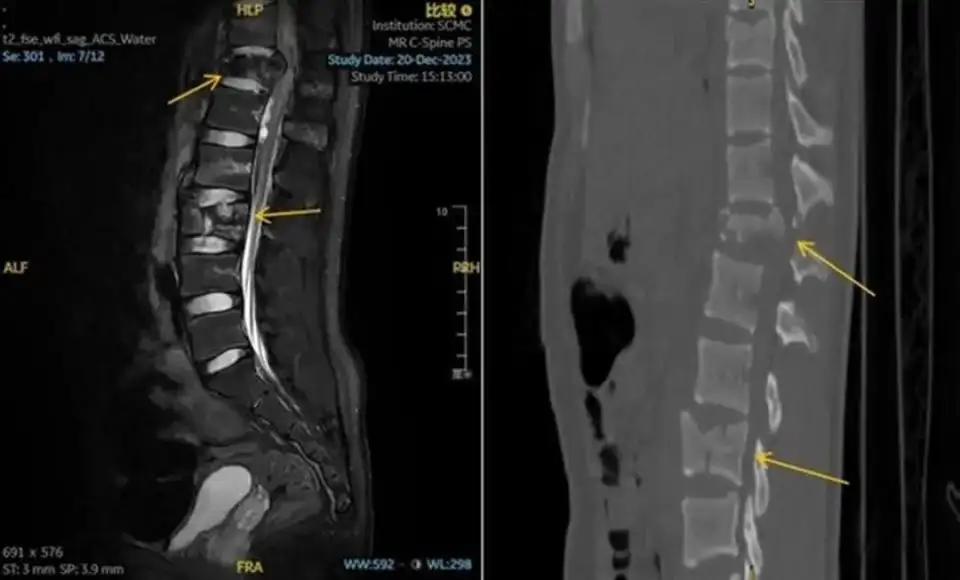

当时他虽意识清醒,但双下肢已无法站立,感觉麻痹。家属立即拨打120将孩子送至上海交通大学医学院附属上海儿童医学中心急诊。入院后, CT结果提示其胸、腰椎多发爆裂骨折,情况十分危急。

术前CT显示,孟迪的胸、腰椎多发爆裂性骨折伴移位(图源:上海儿童医学中心)